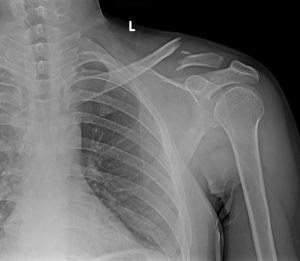

Omuz kırığı, omuz eklemini meydana getiren, proksimal humerus üst ucunda görülen kırıktır.

Omuz kırığı tanısında fizik muayenenin yanı sıra radyolojik inceleme yapılarak da tanı koyulur. Fakat kırıktaki parçalanma ve de ayrışma miktarı, açılanmanın olduğu bölgenin derecesi tedavi yolunda çok büyük bir önem arz eder. Bu sebeple bir çok hastada tedavi yönteminin seçiminde omuz ekleminin bilgisayarlı tomografi (BT) kullanılarak görüntülenmesi ve sonra da uygulanacak olan tedavi yöntem kararı verilir.